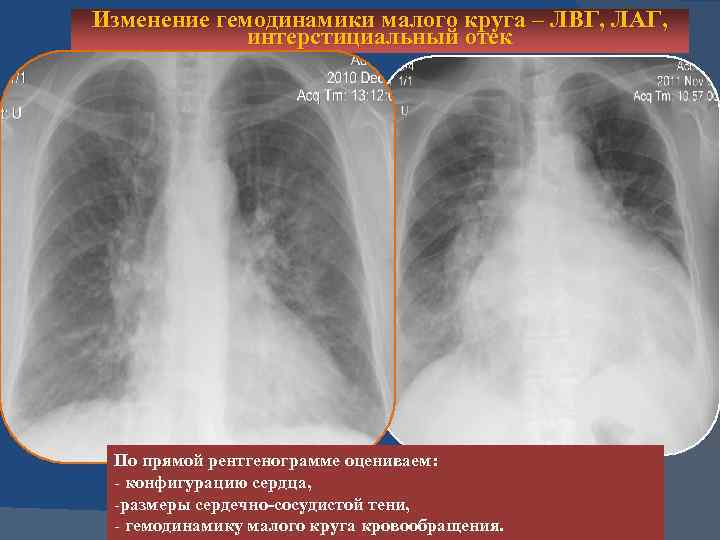

Изменение гемодинамики малого круга – ЛВГ, ЛАГ, интерстициальный отек

Изменение гемодинамики малого круга – ЛВГ, ЛАГ, интерстициальный отек По прямой рентгенограмме оцениваем: - конфигурацию сердца, -размеры сердечно-сосудистой тени, - гемодинамику малого круга кровообращения.